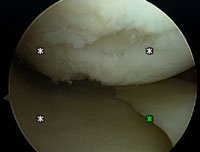

Articular cartilage damage is most reliably diagnosed with an arthroscopic examination of the joint. In this procedure, a tiny fiberoptic scope is inserted into the joint. The doctor uses this scope to visually assess the damage.

Shaving or Debridement

This arthroscopic technique has been popular for 20 years and has had very satisfactory results for over 75% of patients. It is a common treatment for patients with a cartilage defect that has not worn all the way down to the bone, especially under the kneecap. This procedure is also used in the more arthritic knee when other resurfacing techniques are not appropriate. Using special arthroscopic instruments, the physician smoothes the shredded or frayed articular cartilage. Ideally, this treatment will decrease friction and irritation, reducing the symptoms of swelling, noise, and pain.

Microfracture or Abrasion

This technique encourages the growth of new cartilage into a defect. This is a well-accepted technique that is a common procedure for patients with damage through the full thickness of articular cartilage, all the way down to the bone. Using an arthroscopic procedure, the base of the damaged area is scraped to create a bleeding bed of bone. Blood is essential for healing. Small holes are then "picked" into the defect with a special instrument, allowing blood vessels and bone marrow cells to be in contact with the exposed cartilage defect. Bone marrow then fills the defect promoting the formation of a clot, which will eventually mature into firm scar cartilage. Research has shown that this tissue is a hybrid cartilage. Although this newly grown cartilage is durable and can function for many years, it may not have the same durability or strength as the original hyaline cartilage that existed before the injury.